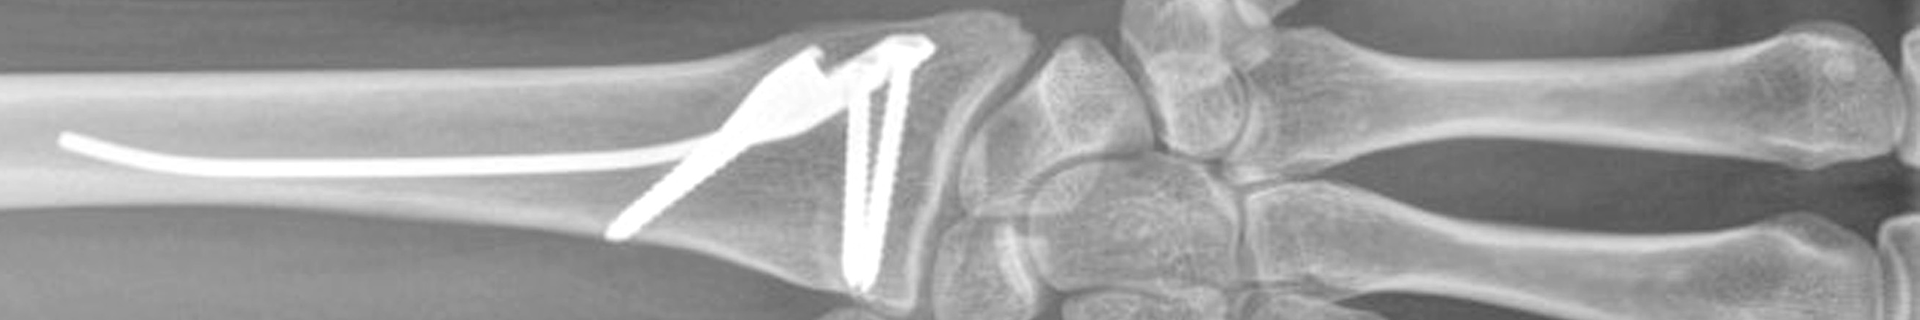

Introducing the new Distal Radius Intramedullary Nail (DRIM-Nail) for the fixation of extra-articular fractures

In response to various clinical complications following fixation of distal radius fractures using CRPP and ORIF techniques, a collaboration between the University of Balgrist, Disrad AG, the AO Technical Commission's Hand Expert Group, the AO's Development Incubator and 41medical has witnessed the design and development of an intramedullary implant for extra-articular distal radius fractures.